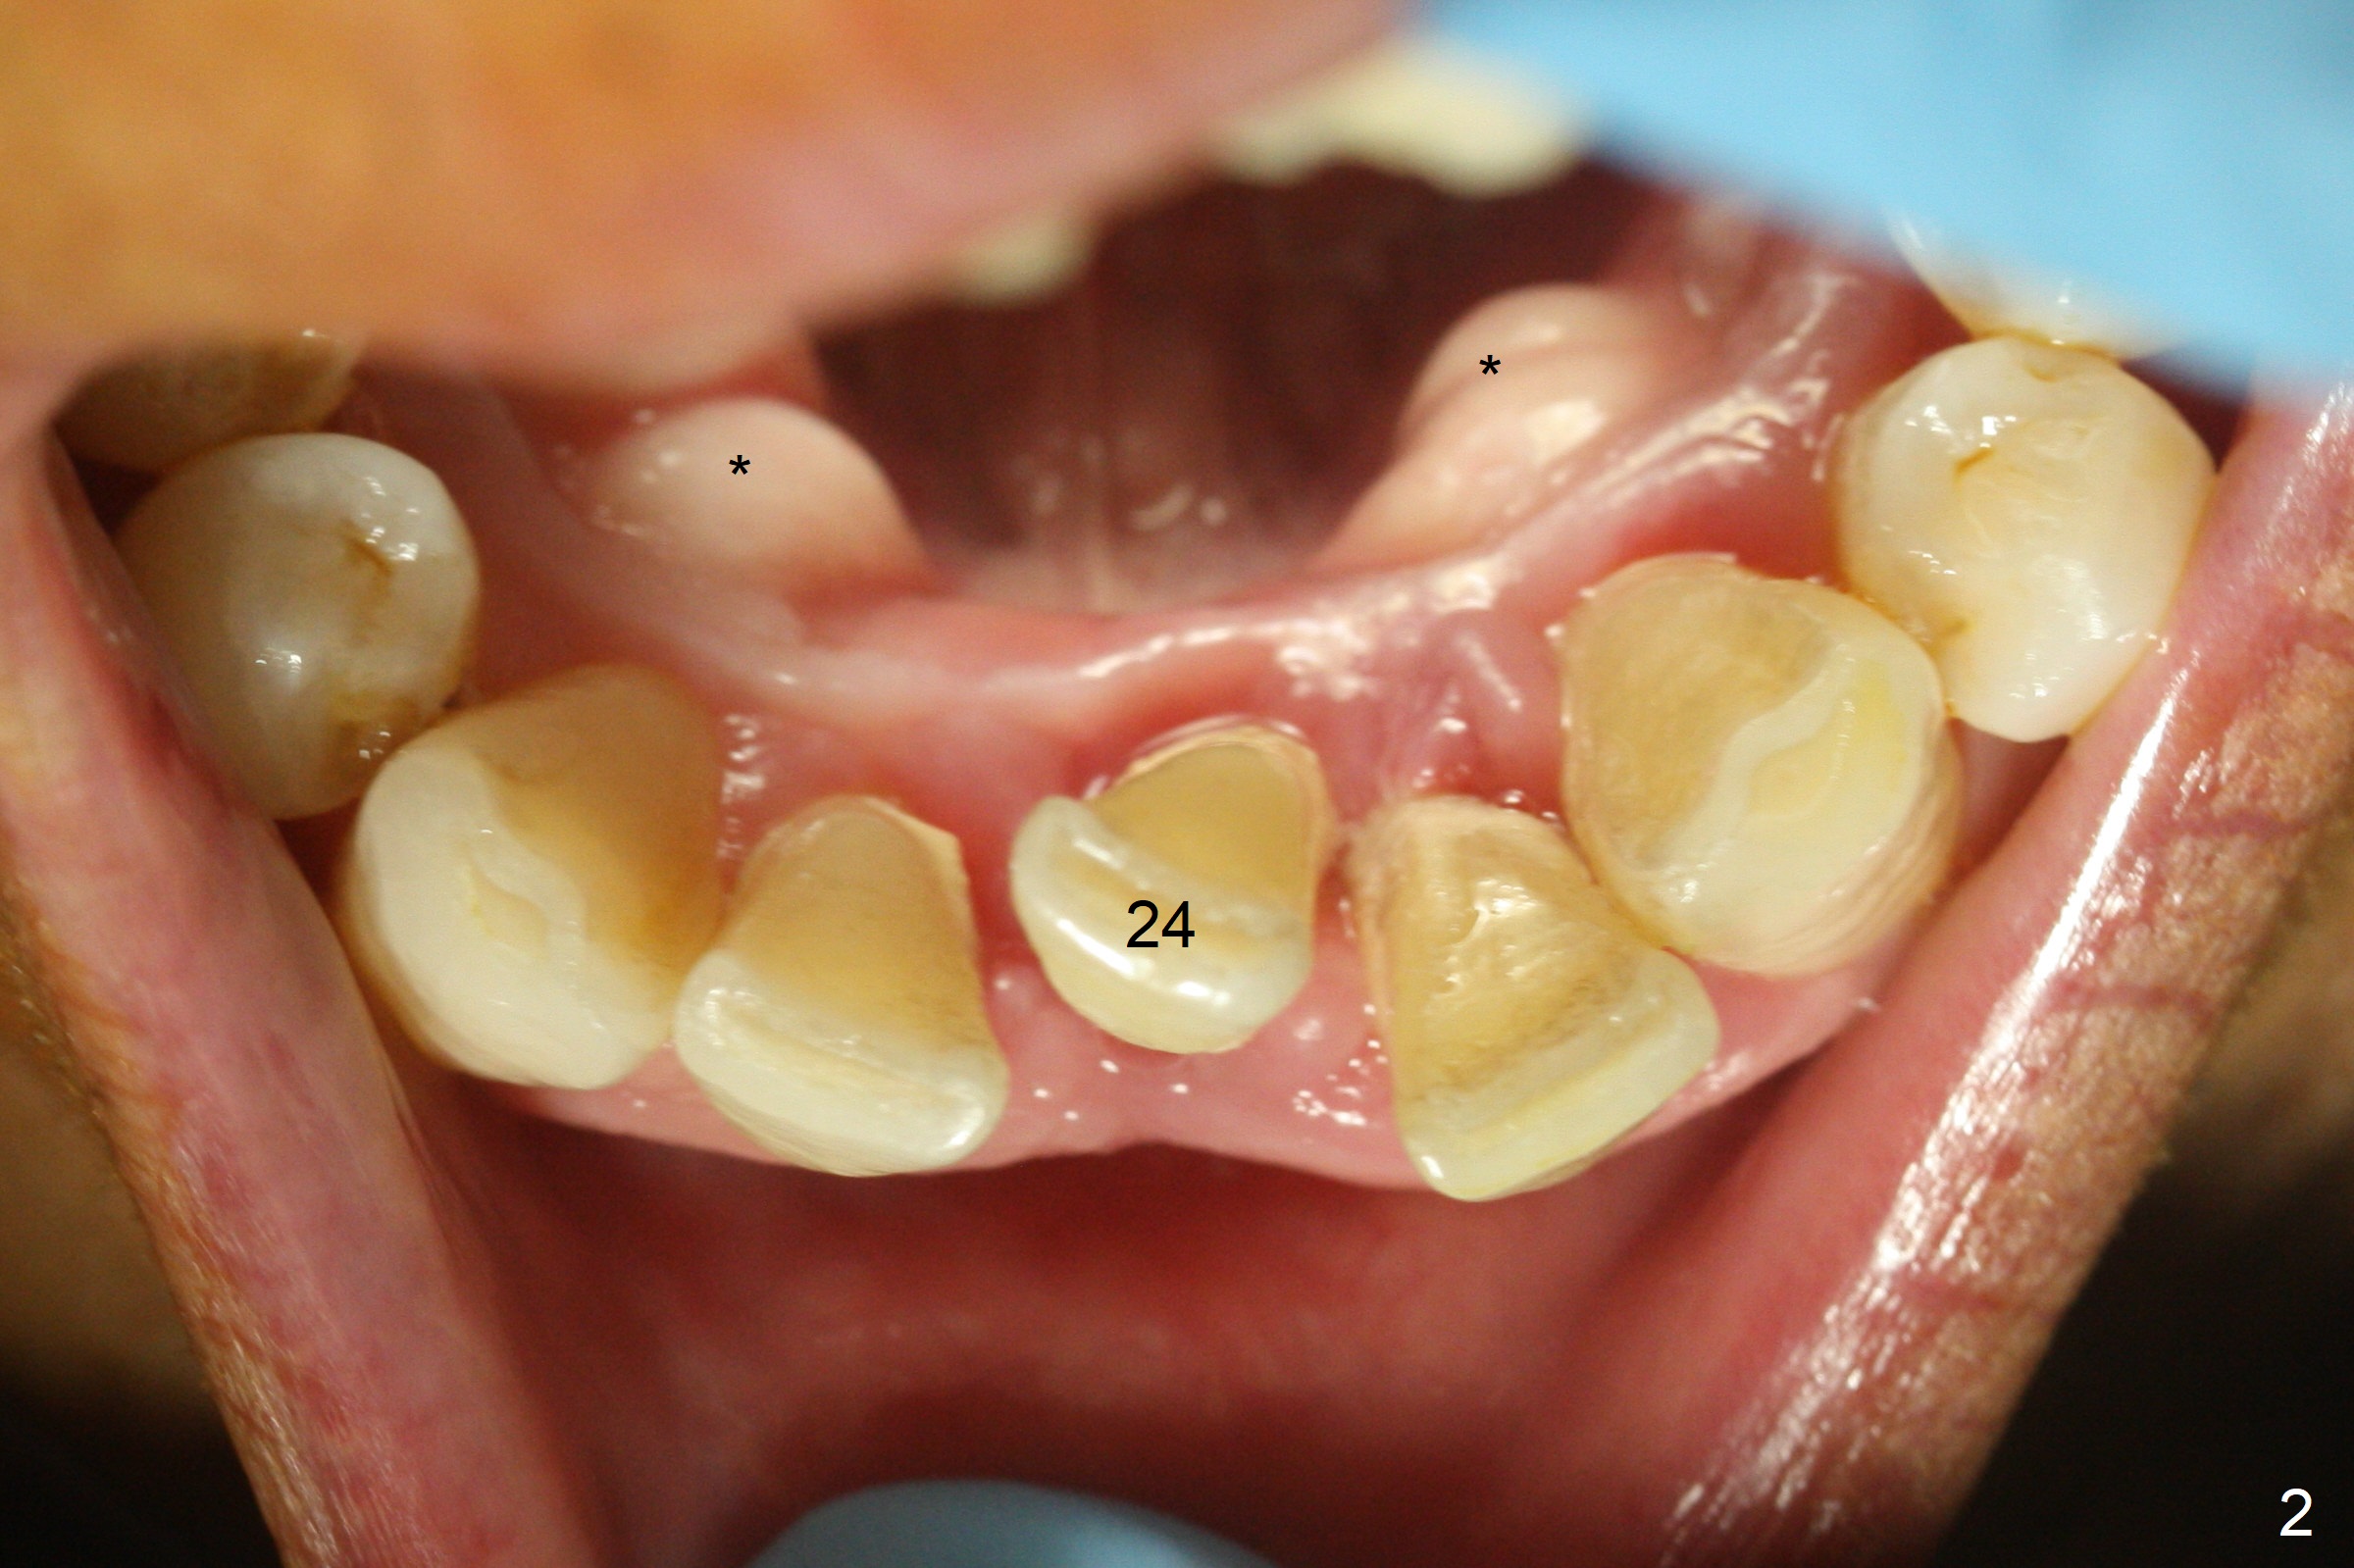

When the patient returns for implant placement 1.5 years after the last treatment (SRP), the tooth #25 has exfoliated, whereas the tooth #24 is severely displaced (Fig.1-3).  In fact the buccolingual plates are found to be lost after extraction, corresponding to change in gingival color indicated by an arrowhead in Fig.1.  Initial osteotomy with 1.2 mm drill is parallel to the terminal branches of the Incisive Canal (Fig.4 arrowheads).  Since the gingiva is as thick as 7.5 mm (Fig.3 arrow), a 3x14 mm 1-piece implant with 4 mm cuff is placed (Fig.5); three implant threads are outside the native bone; with allograft (*) placed and the neighboring crests being coronal to the threads, the chance of periimplantitis should be remote.  An immediate provisional is fabricated to contain the graft in place.  Meanwhile the tooth #2 is symptomatic with crack.  The top 3 threads appear to be contacted by the newly formed crestal bone 6 months postop (Fig.6 *).  Bone appears to have grown into the space between implant threads 6 months post cementation (13 months postop).